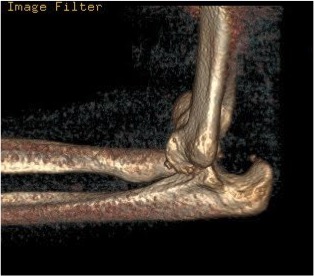

Fracture of the proximal ulna with dislocation of the radial head (a Monteggia fracture). Same patient's Intra-operative x-ray with ulna plated and radial head in correct position